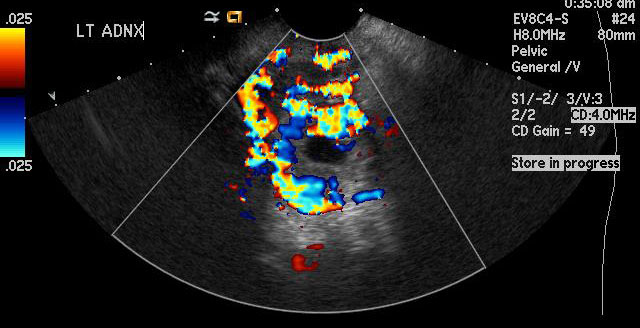

Figure 4

This image has color Doppler which shows increased vascularity in the left adnexa in a ring-like pattern concerning for an ectopic pregnancy |